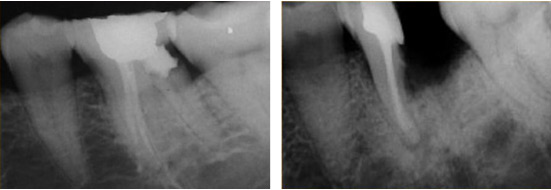

Гемисекция корня проводится на зубах молярной группы нижней челюсти, в том случае если один из их корней имеет значительные деструктивные поражения.

Такая хирургическая манипуляция относится к зубосохраняющим операциям, суть которой заключается в удалении одного из корней многокорневого зуба вместе с прилегающей коронковой частью и воспаленными периапикальными тканями.

Оставшаяся часть, не затронутая патологическим процессом и способная выдержать функциональную нагрузку сохраняется.

Гемисекция корня зуба позволяет сохранить живую единицу при запущенных (хронических) формах заболевания, возникших, например, по причине некачественного эндодонтического лечения, в результате которого оставшиеся патогенные микроорганизмы продолжают размножаться локализуя очаг воспаления в области корня зуба, при этом воспалительный процесс распространяется дальше, разрушая коронку и инфицируя ткани в околоверхушечной области.

Первый способ предполагает осуществление доступа к корню через корону. Для этого врач производит распиливание коронковой части до зоны бифуркации (т.е. до места где начинается расхождение корней). После этого производится экстракция поврежденного корня.

Второй способ заключается в проведении разреза десны до кости и отслаивания слизисто-надкостничного лоскута. Далее, в проекции корня высверливают фрагмент кости для формирования оперативного доступа. Через образованное отверстие отсекают и извлекают корень. Такая техника применяется и в случае выявления кистозного образования в периапикальной области.

Через перфорированное окошко иссекают околокорневую кисту, полость тщательно вычищают от остатков патогенных тканей, обрабатывают антисептическими препаратами и, в зависимости от размера кисты, заполняют остеозамещающим материалом. Затем лоскут возвращают на место и рану зашивают.